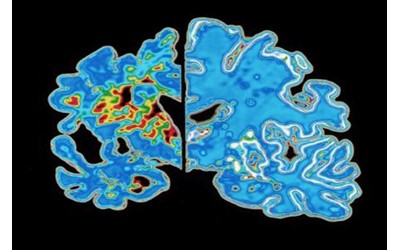

پروتئین‌های تاو غیرطبیعی می‌توانند رشته‌های درهم‌تنیده‌ای تشکیل دهند که ارتباط میان سلول‌های عصبی مغز را مختل می‌کند. آزمایش‌های تصویربرداری مغزی که این توده‌های درهم‌ تنیده تاو را شناسایی می‌کنند، گاهی در تشخیص آلزایمر استفاده می‌شوند، و مطالعات اولیه نشان می‌دهد که چنین آزمایش‌هایی شاید بتوانند زمان بروز علائم آلزایمر را نیز پیش‌بینی کنند. اما شیندلر می‌گوید این روش‌های تصویربرداری دشوار و پرهزینه هستند. در همین حال، پژوهشگران در حال بررسی آزمایش‌های ساده‌تر مبتنی بر خون هستند که می‌توانند تاو را نیز ردیابی کنند. برای مشخص کردن «ساعت» مولکولی خود، شیندلر و همکارانش از داده‌های آزمایش‌های خون و ارزیابی‌های شناختی 600 فرد سالمند که در دو مطالعه بزرگ آلزایمر شرکت داشتند استفاده کردند. به‌طور خاص، آن‌ها بر نوعی از تاو غیرطبیعی به نام p-tau217 تمرکز کردند. پژوهشگران دریافتند نسبت p-tau217  به تاو طبیعی در خون، مدت‌ها پیش از آغاز علائم شناختی شروع به افزایش می‌کند. شیندلر می‌گوید سرعت افزایش p-tau217 میان افراد به‌طرز قابل توجهی یکنواخت بود. این موضوع به گروه اجازه داد مدلی طراحی کند که بر پایه سن و سطح p-tau217، بتواند زمان بروز علائم آلزایمر را با حاشیه خطای سه تا چهار سال برآورد کند.